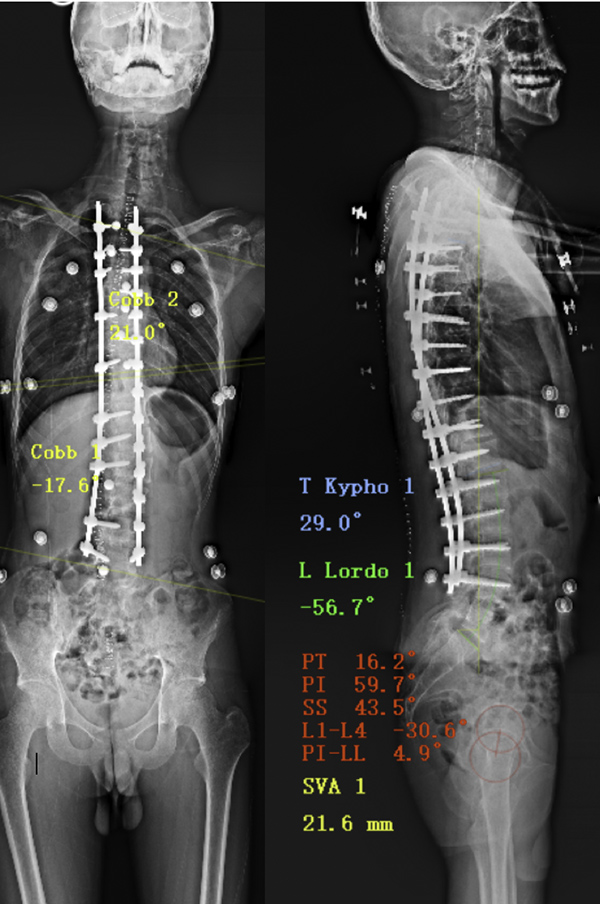

·Treatment 治疗方式 (术者:吴浩主任)

椎弓根螺钉植入,脊柱侧弯矫形术

治疗目的:减少青春期脊柱曲度增加,预防可能出现的呼吸障碍及脊柱疼痛,改善外观。

患者术后矫形良好

脊柱侧弯角度超过45°,可以通过前路、后路或联合方法进行手术。通过植入椎弓根螺钉,在三个维度上进行矫型(图5)。常说的矫正手术是矫正融合手术,矫正融合手术就是在体内放入金属的钉棒支架,这个金属支架可以将弯曲的脊柱拉直并维持,相当于放在体内的金属支具。单靠支架维持还不够,手术置入支架的同时还进行了植骨术,就是在脊柱背侧放置了颗粒骨,这些颗粒骨愈合后会将脊柱固定住。所以,其实术后半年左右金属支架就失去支撑脊柱的作用了,那时脊柱曲度的维持主要靠融合了的颗粒骨[7]。